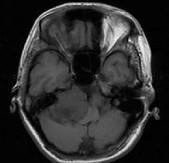

问题 女,45岁,右耳听力下降半年余,CT检查如图,最可能诊断为()

选项 A.继发性胆脂瘤 B.脑膜瘤 C.三叉神经瘤 D.原发性胆脂瘤 E.听神经瘤

答案 E